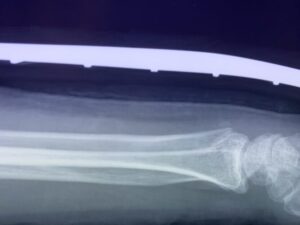

さわやか千葉県民プラザ(前腕骨下端部骨折)

春日部市市民活動センター(前腕骨骨幹部骨折)

第26回整骨研究会「賜恩」研修会開催